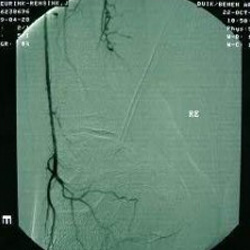

Ischemie is naast de neuropathie en infectie een belangrijke complicatie bij suikerziekte en leidt tot de aantasting van de bloedvaten. Hierdoor kunnen doorbloedingsstoornissen ontstaan in de onderbenen en de voeten en spreken we van een ischemische voet.

Uit een grote Europese studie (van ruim 1200 patiënten) bleek dat vrijwel de helft van de patiënten met voetwonden een doorbloedingsstoornis had van de voet.